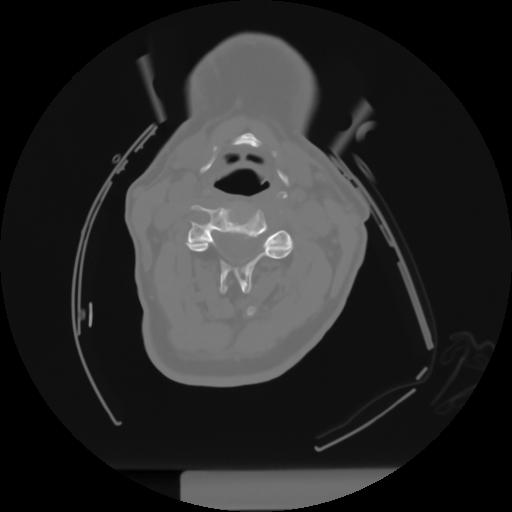

10 P.BLANDAS,,Axial,2.0,P.BLANDAS,,